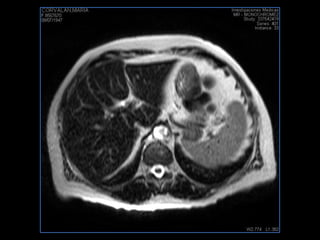

PROTOCOLO abdomen COR T2, AXIAL supresion grasa AX T1 +SAG T2  CON   GADOLINIO :  COR T1+AX T1(DIN) SAT: NO  FASE: RL THK: 6MM  COIL:  GAP: (FACTOR 1.4) 2MM FOV: 40 CM NEX:2 SINCRONIZACION RESPIRATORIA EN 3 O 4 CICLOS ALE